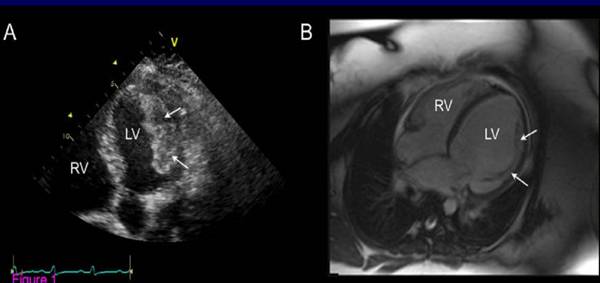

PPCM患者左心室内附壁血栓